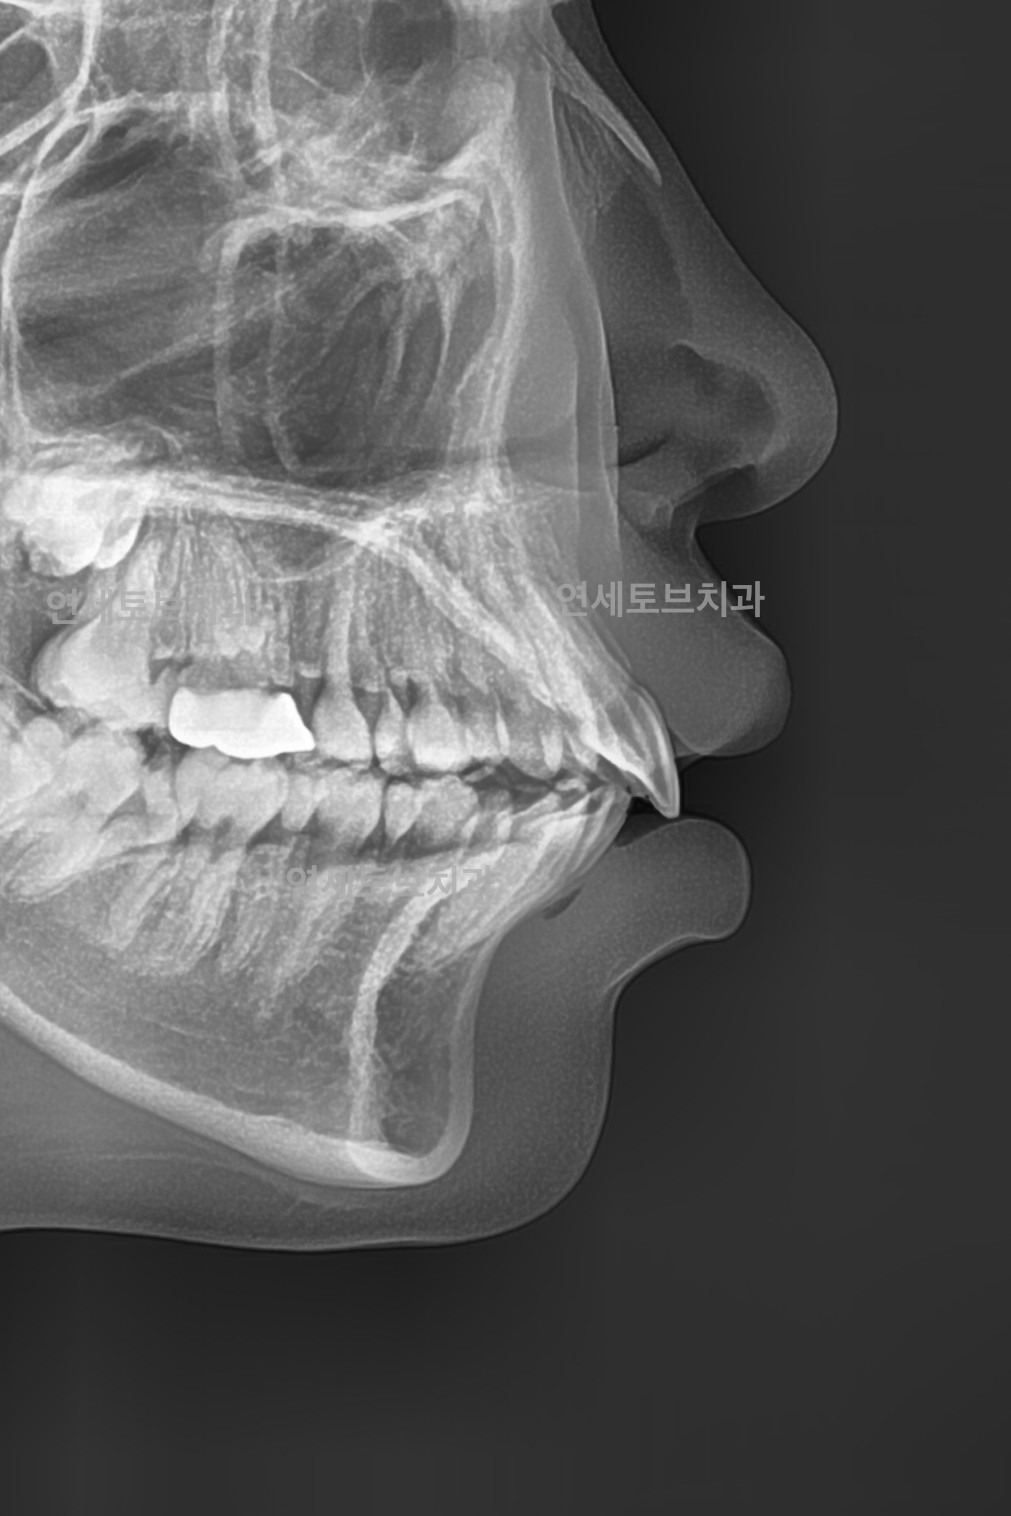

After

돌출입은 윗니나 아랫니(또는 둘 다)가 정상적인 위치보다 앞으로 튀어나온 상태를 말합니다.

이로 인해 입술이 앞으로 돌출되어 보이고, 측면 얼굴 프로필에서 특히 두드러지게 나타납니다.

한국인을 포함한 동양인에게 비교적 흔하게 나타나는 부정교합 유형입니다.